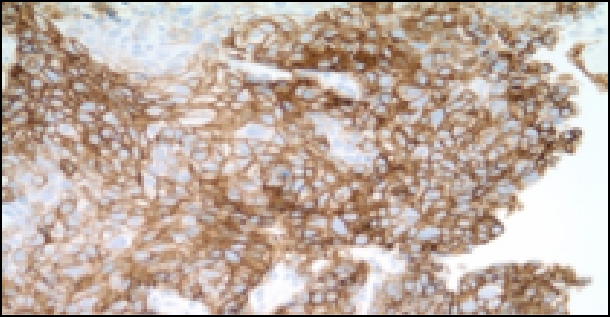

Az elvégzett immunhisztokémiai vizsgálatok EGFR, ALK, KRAS negativitás mellett PD-L1 90% pozitivitást mutattak.

kép